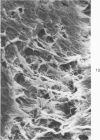

Common biliary ducts of 32 adult mongrel dogs were ligated for a period of 2 days to 6 weeks. Sham-operated animals served as controls. Bile ducts were removed at sacrifice, and biophysical, morphologic, and biochemical parameters were measured. Our study shows that biliary duct ligation results in an immediate increase of intraductular pressure and is followed quickly by significant increase in the rate of collagen synthesis and the activity of prolyl hydroxylase. Histologic data show subepithelial inflammation followed by marked increases in periductular fibrosis. This fibroproliferative response is paralleled by peak levels of prolyl hydroxylase activity at 2 weeks prostligation. Paradoxically, bile ducts continuously distend throughout the ligation period despite increased fibroplasia. We present here the first topographic (SEM) study of normal and ligated common bile duct epithelium. Following 2 weeks of ligation large crater-like fenestrae are seen ductular epithelial surfaces. This is followed by focal epithelial sloughing. We speculate that the continuous distention and epithelial necrosis seen in the present study may be due to biliary stasis and/or subepithelial infiltration of bile through epithelial fenestrae. This hypothesis is supported by our studies which show that collagen extractibility is markedly increased by the addition of bile to the homogenate.